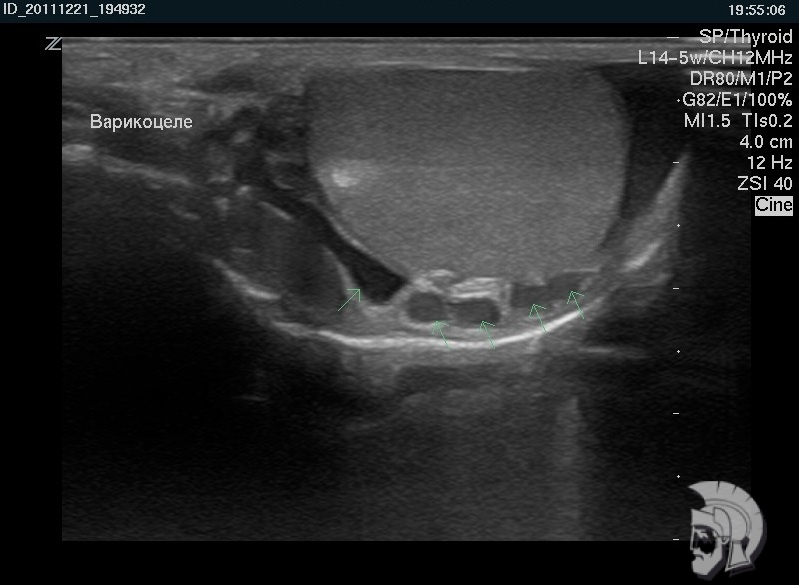

Резкая боль в паху заставила обратиться к врачу. После диагностики на специальном аппарате УЗИ было назначено скорое лечение. Спасибо за быструю диагностику и лечение! Очень тактичный и профессиональны й персонал! С ув. Михаил Васильевич, г.Пятигорск.